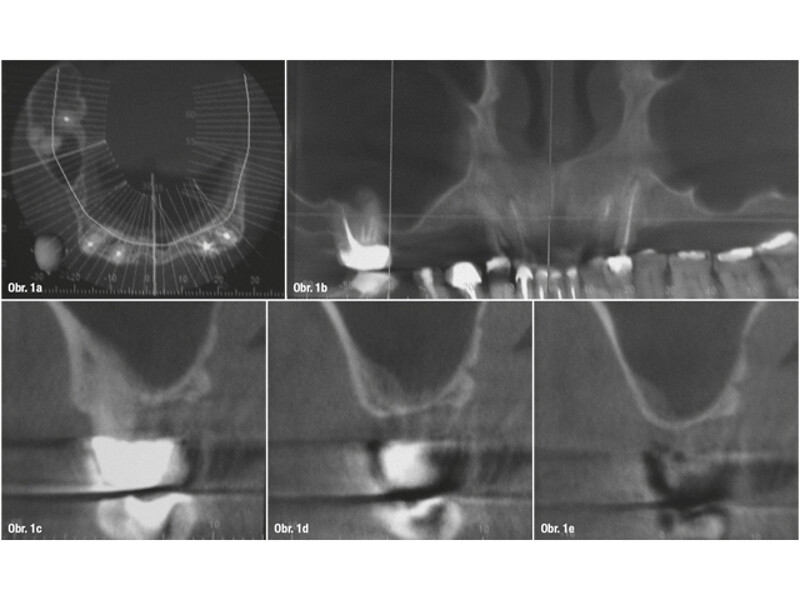

Minimálně invazivní krátké a úzké implantáty